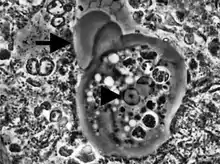

Entamoeba cells are small, with a single nucleus and typically a single lobose pseudopod taking the form of a clear anterior bulge. They have a simple life cycle. The trophozoite (feeding-dividing form) is approximately 10-20 μm in diameter and feeds primarily on bacteria. It divides by simple binary fission to form two smaller daughter cells. Almost all species form cysts, the stage involved in transmission (the exception is Entamoeba gingivalis). Depending on the species, these can have one, four or eight nuclei and are variable in size; these characteristics help in species identification.